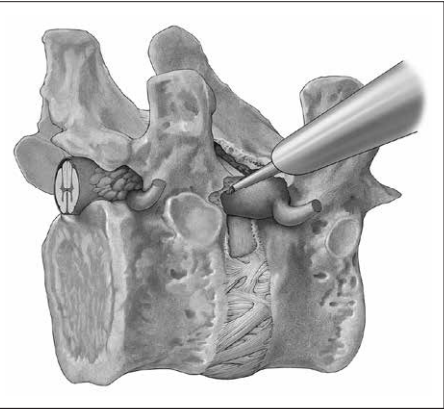

3. 通常必须通过切除小关节骨质来拓宽椎间孔,以便进入椎间孔或椎管;

4.若存在钙化,则必须从椎体后缘切除椎间盘周围部分骨质。这样可在不刺激脊髓的情况下,从同侧到中线进行间接或直接的前路减压。这样的方法叫做脊髓盒状切除减压术(Box-shaped resection)。

2. 去除小关节骨质后,可适当放平,配合25°内镜可以清晰观察脊髓;

3. 必须特别小心切除对侧,因为25°内镜视野允许脊髓前下方的良好视野,并不倾向于进行对侧减压;